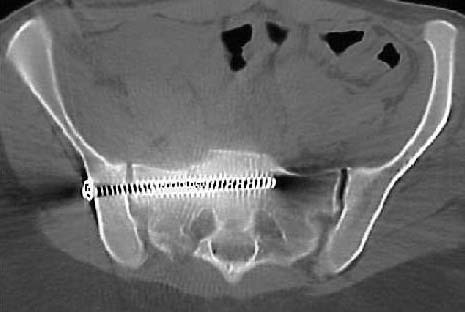

The screw has been inserted after an acceptable reduction. If you had chosen a starting point 3mm more posteriorly, even with the same aim, then you would have avoided her SI articular surfaces and maintained the same balanced implant length...see the sacral postop CT axial image...is the left sided sacral linear lucency at the screw tip an artifact, or fracture that we initially didn't identify?